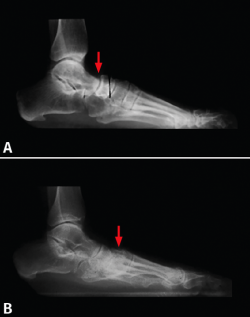

Figura 4. Pie plano por disfunción del tibial posterior. La flecha señala: A: subluxación talonavicular; B: subluxación navículo-cuneiforme medial.

Ello fue motivo de una presentación el año 1996 en la Societat Catalana de Cirurgia Ortopèdica i Traumatologia por A. Viladot Voegeli et al.(7), que estudiaron este tema: se analizaron las radiografías de perfil en carga de 30 pies planos secundarios a una disfunción del tibial posterior. Se pudo observar que 10 pies (33%) presentaban una subluxación talonavicular. En 11 pies (37%) la subluxación se encontró entre el navicular y el CM (Figura 4) y 2 pies (7%) presentaban una pequeña subluxación mixta entre el talus, el navicular, el CM y el primer metatarsiano. Por último, 7 pies (23%) no presentaban ningún tipo de alteración en la congruencia articular.